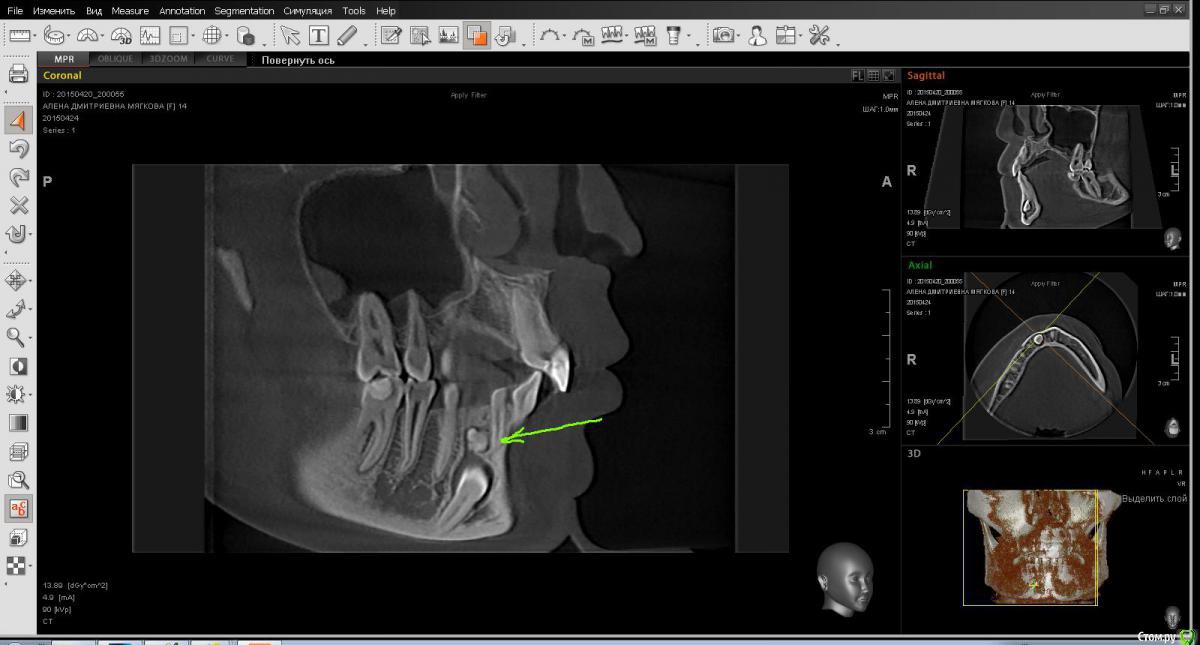

sgeorge Опубликовано 24 апреля, 2015 Автор Поделиться Опубликовано 24 апреля, 2015 Вот некоторые срезы. Вопрос в том, стоит ли браться за ортодонтию. Ортодонта сегодня нет, спросить не могу. Ссылка на комментарий

sgeorge Опубликовано 24 апреля, 2015 Автор Поделиться Опубликовано 24 апреля, 2015 Как-то криво прикрепились, сорри.Думаю, что с таким крючком на апексе ортодонтия отпадет? Тогда стоит ли удалять в настоящий момент или дождаться завершения роста челюсти? Ссылка на комментарий

krokomot Опубликовано 24 апреля, 2015 Поделиться Опубликовано 24 апреля, 2015 Клык то молочный во рту, без ортодонтии все равно не обойтись так что можно попробовать зуб вертикально почти стоит, только кортикалку желательно бы удалить по ходу выдвижения (постепенно). На стрелке думаю одонтома при раскрытии убрать. Ссылка на комментарий

CToMaToJlor Опубликовано 24 апреля, 2015 Поделиться Опубликовано 24 апреля, 2015 А мне кажется, вытянуть не получится. Удаление , ортодонтия, имплантация. Там же крюк на корне. Ортодонт не возьмется. Имхо Ссылка на комментарий

sgeorge Опубликовано 29 апреля, 2015 Автор Поделиться Опубликовано 29 апреля, 2015 Значимость клыка вполне ясна. Сильно смущает загнутая верхушка корня, позволит ли это переместить зуб на столь немаленькое количество милиметров Ссылка на комментарий

krokomot Опубликовано 29 апреля, 2015 Поделиться Опубликовано 29 апреля, 2015 Значимость клыка вполне ясна. Сильно смущает загнутая верхушка корня, позволит ли это переместить зуб на столь немаленькое количество милиметровПочему это вас смущает? Когда ортодонт корпусно перремещает зуб, площадь костного сопротивления гораздо больше, чем какой-то крючок, крючок будет мешать удалению, но не как не перемещению. 2 Ссылка на комментарий